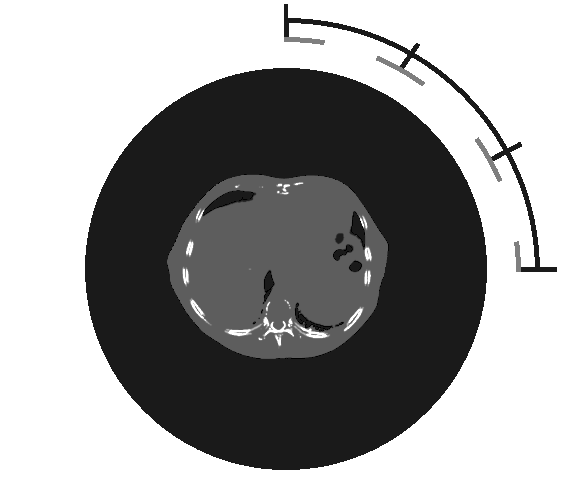

The algorithm is also tested on three patient cases. The data is a liver case, a head and neck case, and a prostate case with CTs and ROIs from the TROTS dataset. The data was imported into a research version of RayStation 2023B and proton arc plans were using a dynamic full revolution PBSArc with 180 energy layers were generated. Each case had three objective functions: a robust min function and robust max function on the PTV, and a non-robust dose fall-off function on the external. The thresholds for the min and max functions were set to the target dose Gy. The dose fall-off function was weighted 1000 times lower than the other functions. The robustness included 21 scenarios, created by 3 mm position uncertainty and 3% density uncertainty. Each case was allowed to run for 100 iterations until spot filtering, and then for 50 iterations more. The target dose was 50 Gy for the liver case, 70 Gy for the prostate case, and 46 Gy for the head and neck case. Each case consisted of 30 fractions. The dose distribution of the prostate case can be seen in figure 4.